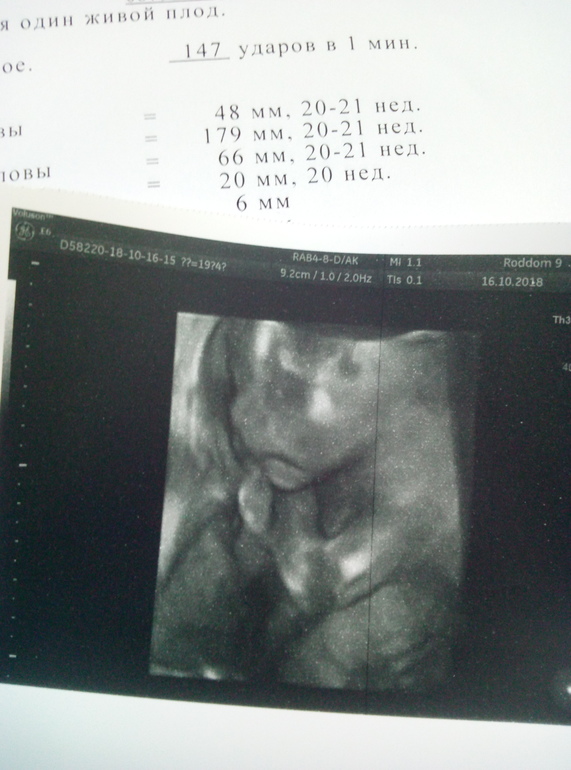

Девчонки привет. Прошли сегодня второй скрининг, у нас все хорошо, уже точно сказали мальчик))) опережает малыш,по УЗИ 20-21 неделя, а по м 19+4, вес уже 341 гр.😍😍😍 Врач даже включила мне 4д посмотреть малыша и сделала фото( правда чёрно-белое) . Пока делали УЗИ малыш всё пытался датчик пнуть ножкой, так миленько))) вообщем счастью нет придела, не могу уже дождаться нашей следующей встречи. 😘😘

Вот мой сладенький человечик. 😚😚